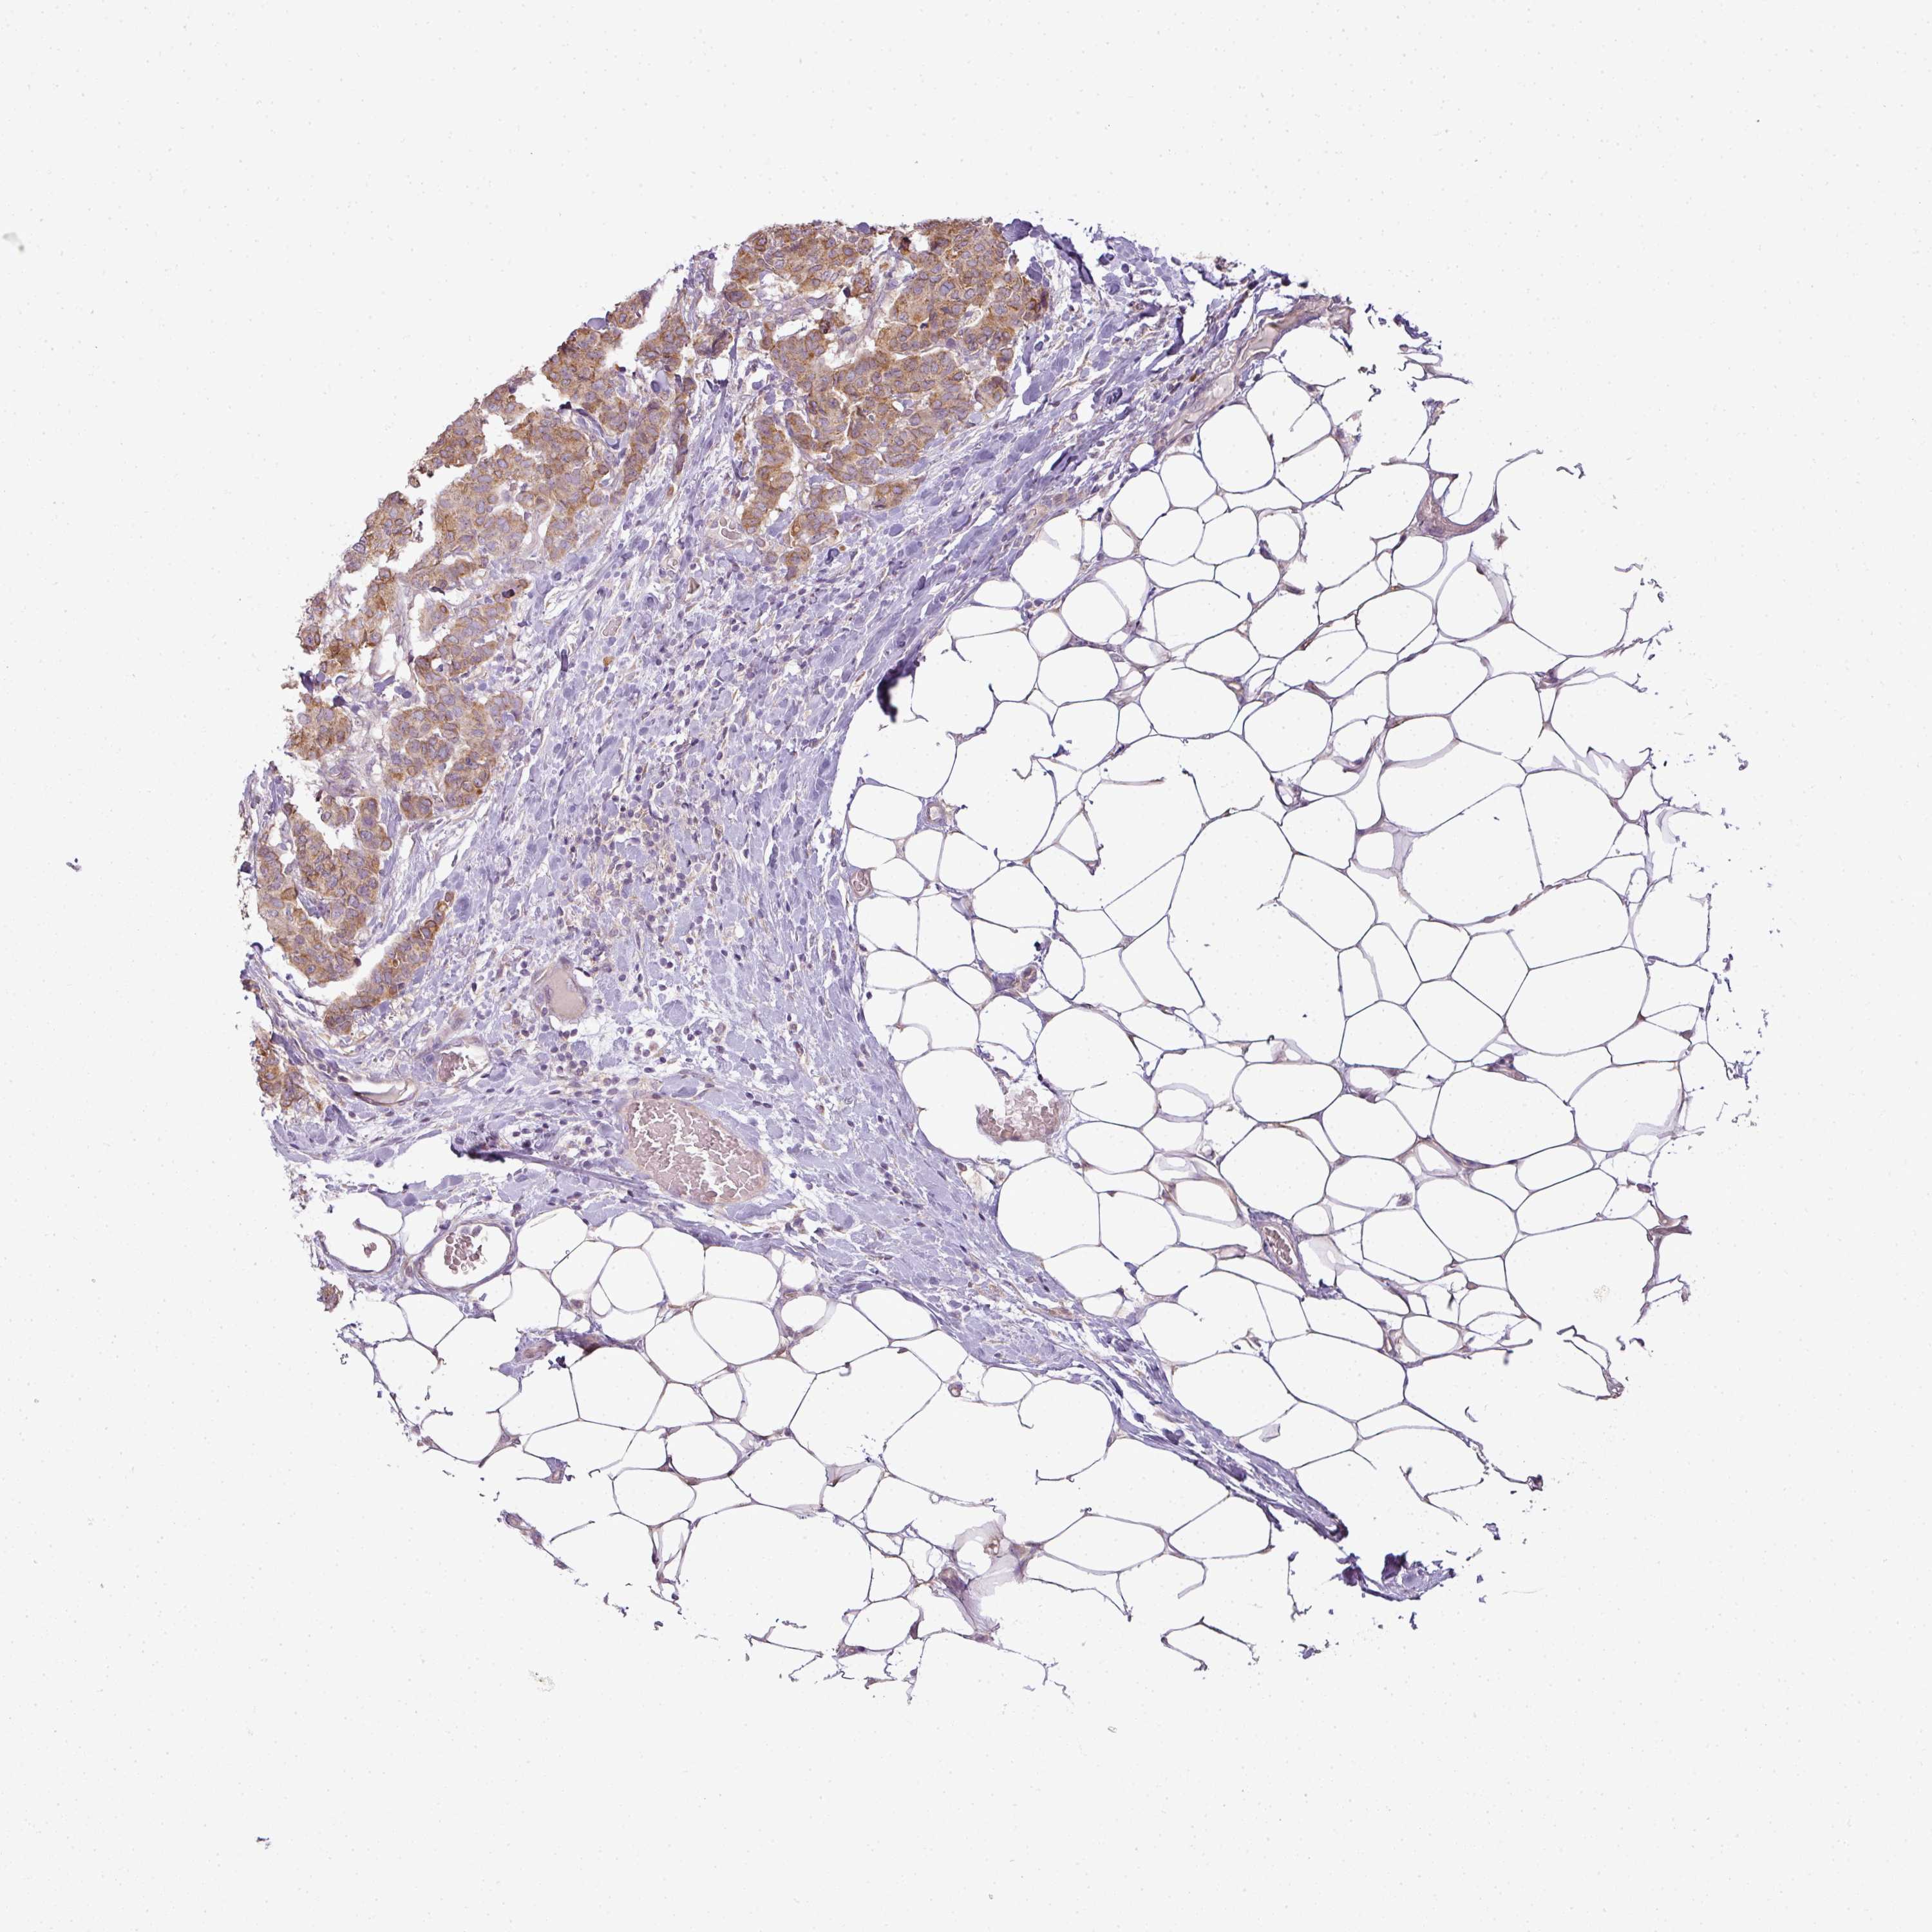

BRCA TCGA BRCA VALIDATION PROTEIN EXPRESSION

ANTIBODIES

AND

VALIDATION